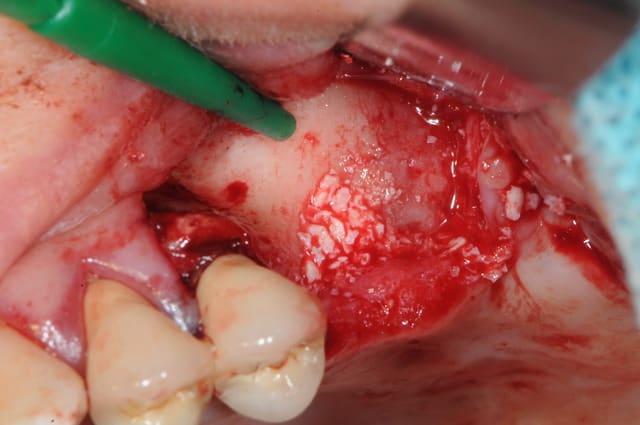

je fais bref!

déjà ne fais pas la même chose que moi; décales ton trait d'incision par rapport à l'entrée de la CBS

- coupes la communication entre la membrane de Schneider et la muqueuse (ici, c'était à moitié de la gencive et de la boule de Bichat mélangée avec du tissus de granulation)

- cautérise avec un bistouri électrique ou un simple bistouri chauffé à blanc.

- refoules le sinus

- prf

- combles (Rog +membrane, ...)

-sutures et le tour est joué.

fais nous des photos, les miennes sont pourries, les piles étaient nazes...

bonne chir, je t'envie.!!

Dsc 3386 ldbnph - Eugenol

Dsc 3388 k915a0 - Eugenol

Dsc 3389 hogsty - Eugenol

Dsc 3390 xrj33k - Eugenol

Dsc 3393 lrovrb - Eugenol

Dsc 3394 did2le - Eugenol

Dsc 3395 vt3d3c - Eugenol

Dsc 3400 qsfbfo - Eugenol

Dsc 3407 pdx0ip - Eugenol

Dsc 3409 mzdzjn - Eugenol

Dsc 3412 rqlbfr - Eugenol

Dsc 3419 etives - Eugenol

Dsc 3422 urehjx - Eugenol

Dsc 3423 nirenc - Eugenol